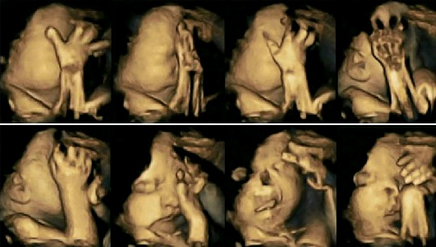

Pamjet e nje foshnje ne barkun e nje nene duhanpirese

Në studim u vu re se foshnjet e nënave joduhanpirëse ishin më të qetë në bark dhe lëviznin më pak në krahasim me foshnjet e palindura të nënave duhanpirëse, që vinin duart më shpesh në gojën dhe fytyrën e tyre.

Nadja Reissland, udhëheqëse e studimit të botuar në revistën “Acta Paediatrica” thotë se në të shumtën e herëve foshnjet lëvizin dhe prekin fytyrën dhe gojën e tyre kur ndjejnë një shqetësim të jashtëm. Mes këtyre shqetësimeve, thotë ajo, futet edhe cigarja.